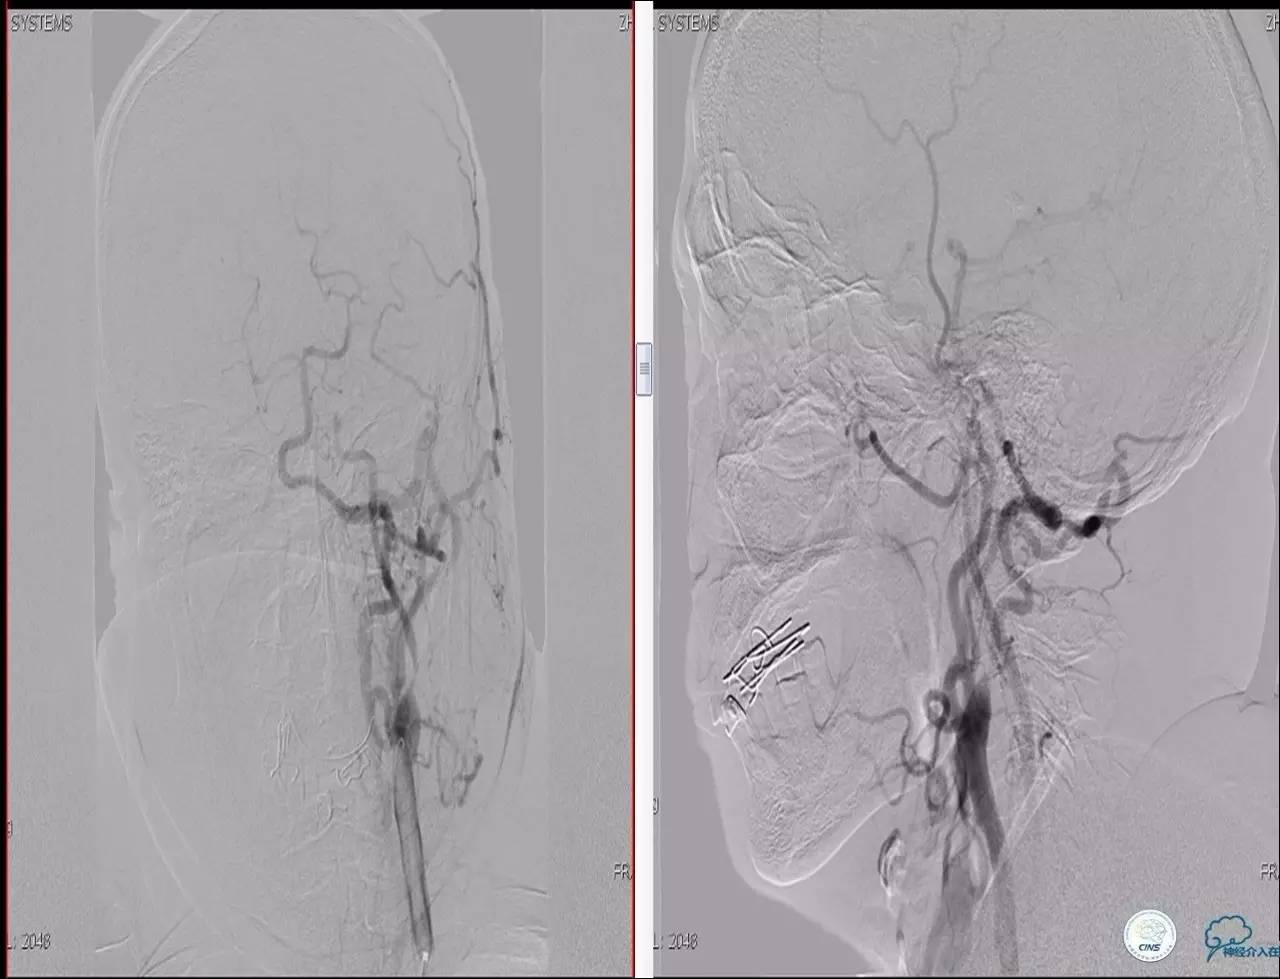

》辅助检查:颈动脉B超显示:左侧颈内动脉起始部狭窄 90%,右侧颈内动脉起始部80%。

Case 2

》男,74岁。

》主诉:突发左侧肢体抽搐伴口角歪斜两月余,右侧肢体抽搐三天余。

》查体:左上肢肌力Ⅲ级,左下肢肌力Ⅳ级,右侧肢体肌力Ⅴ级。

》既往史:高血压病史。